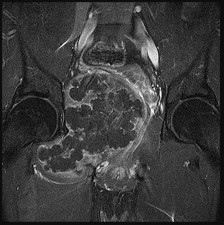

This patient has a dedifferentiated liposarcoma within a preexisting atypical lipomatous tumor. The imaging demonstrates a large fatty mass with increased internal septations proximally (the atypical lipomatous tumor) and a solid enhancing mass distally (the dedifferentiated portion). A biopsy reveals a high-grade liposarcoma. The other diagnostic responses do not reflect sarcomatous transformation of the lesion.

Surgical treatment of a high-grade sarcoma involves wide surgical resection. Radiation decreases local recurrence but does not clearly influence overall survival. The role of chemotherapy in high-grade soft-tissue sarcomas remains investigational; there is a modest (8%-15%) associated improvement in overall survival.

Intramuscular lipomas and atypical lipomatous tumors are treated with marginal resection alone. Radiation therapy for soft-tissue sarcomas may be given before or after surgery. When administered before surgery, patients have a higher wound complication rate but better long-term function attributable to lower rates of lymphedema, fibrosis, and contractures.